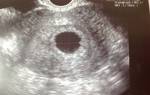

Трансвагинальное УЗИ покажет плодное яйцо в полости матки, когда наступят 4,5 – 5,0 недель беременности. Стоит отметить, что врачи считают продолжительность беременности с первого дня крайних месячных.

То есть не стоит сразу же торопиться на УЗИ, если задержка менструаций составляет 1 – 2 дня. Эхография может показать первые признаки гестации только спустя 3 – 5 суток задержки от даты ожидаемых месячных.

Будущий ребенок на УЗИ выглядит как округлое образование, к пятой неделе его размер составляет несколько миллиметров. После зачатия в матке яйцеклетка закрепляется на 6-10 день с момента оплодотворения и начинает стремительно расти.

В среднем каждый день размер увеличивается на 2 мм.

Самый ранний срок, когда можно достоверно увидеть беременность на УЗИ, – пятая неделя.

Хороший врач на качественной аппаратуре сможет рассмотреть плодное яйцо, эмбрион в нем (он будет выглядеть как маленькая темная полоска длиной 3-5 мм), околоплодные воды; измерить его, оценить форму и прослушать сердцебиение эмбриона. Многоплодную беременность с уверенностью можно будет увидеть на более поздних сроках – примерно на 8-9 неделе.